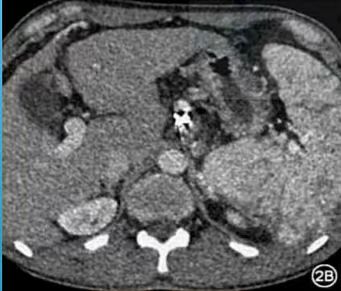

病例四:TIPS+食管胃底静脉栓塞术

2A图示:普通增强扫描,腹主动脉强化明显,金属伪影较重,2B图示:采用100kev单能量重建,发现金属伪影下降,但是碘剂浓度也下降了,这严重影响我们增强图像的强化效果,那该怎么办呢?我们知道随着单能能级的升高,电压也会增加,随着电压的升高,会导致增强时碘剂浓度的下降,所以不能一味地提高能级来抑制线束硬化伪影,这样一定会导致增强碘浓度下降,这个时候就可以运用单能+迭代算法-iMAR的组合来处理。